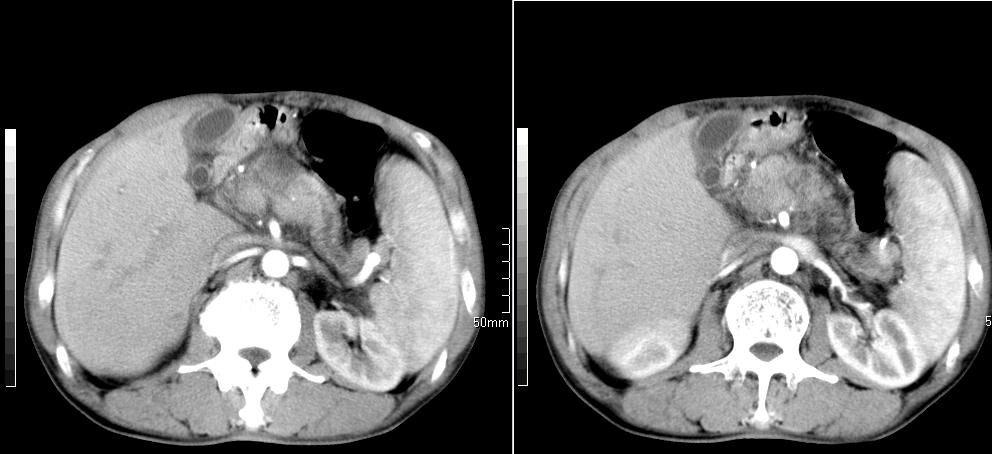

标题: CT26769:男,58岁,腹胀、腹部不适一年余 [打印本页]

标题: CT26769:男,58岁,腹胀、腹部不适一年余

肝右叶后段见小片状略低密度影,边缘不清,轻度强化,内见小血管影通过同,延迟期为等密度,考虑局灶性脂肪浸润。需与血管瘤鉴别。另有胆囊炎、脾大。

肠系膜脂膜炎,胆囊炎,脾大。建议结合临床。鉴别:慢性胰腺炎并假囊肿形成。

1 慢性胰腺炎并假囊肿形成。2 慢性胆囊炎并累及肝边缘!

1)考虑慢性胰腺炎并假性囊肿形成。2) 慢性胆囊炎。3)肝内胆管扩张。

1肝内胆管扩张,性质待定,2慢性胰腺炎胰管扩张,胰腺颈部假囊肿,3肝左叶低密度为小囊肿,4胆囊炎。